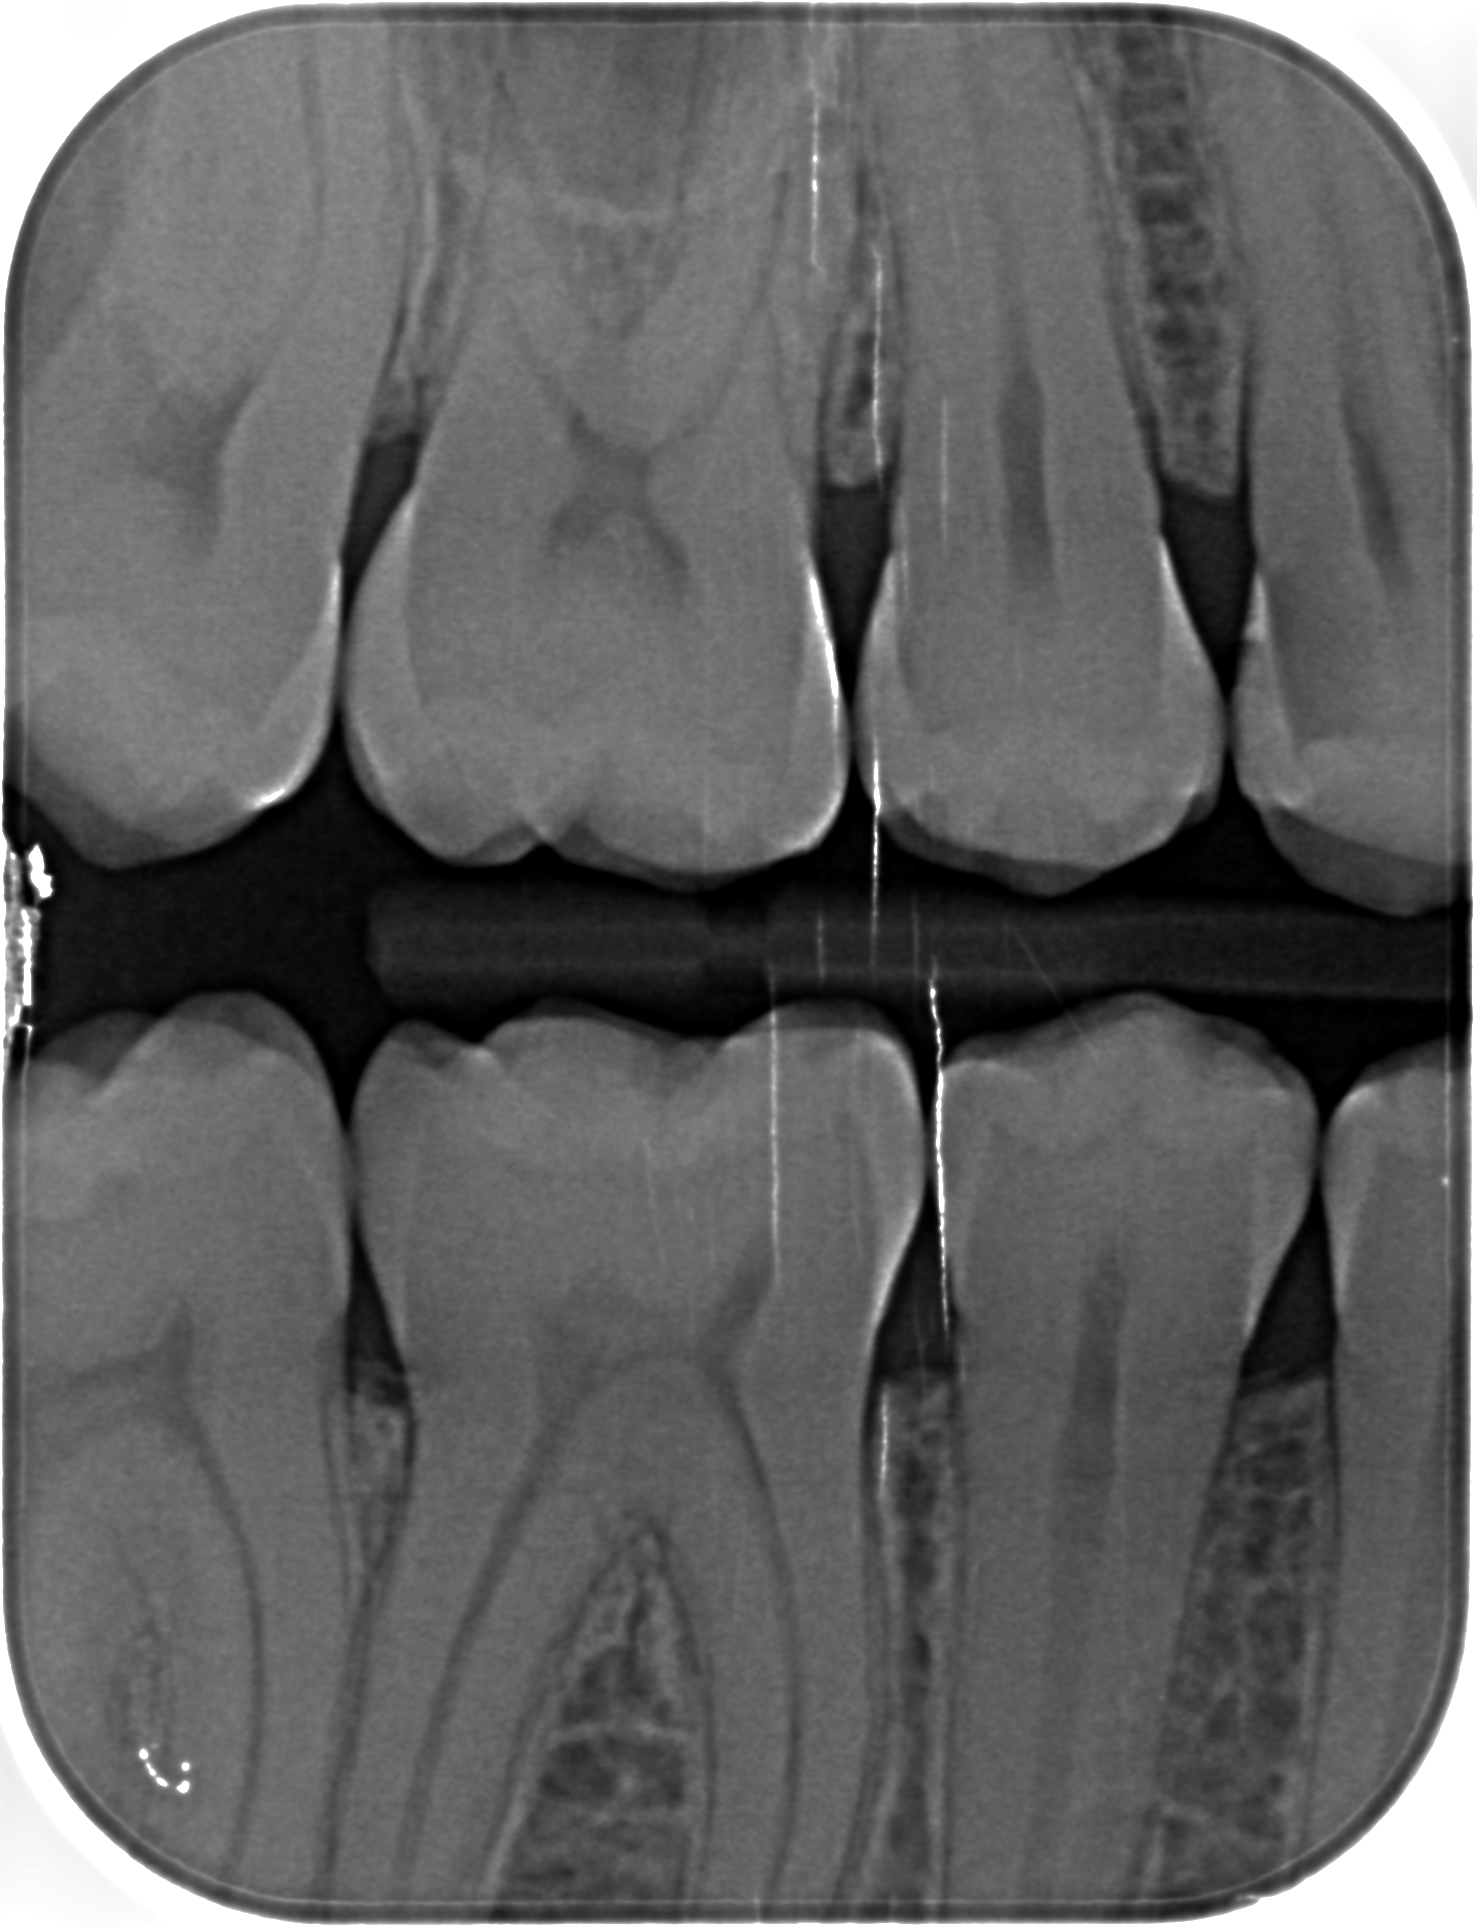

Mi è stata fatta un'altra lastrina 2 settimane fa (è quella con i cerchietti rossi e i numeri dei denti) dove mi è stato detto che c'è una carie interdentale sul 15 (è cerchiata in rosso) e probabilmente anche sul 16 (di fronte a quella del 15) e che sono da otturare al più presto (l'altra carie cerchiata più grossa è già stata curata). Se possibile volevo avere un riscontro anche da voi se queste carie ci sono o no e se sono da otturare. Ho allegato anche le altre lastrine più vecchie (intorno a 6 mesi fa) che riprendono lo stesso lato della bocca Cordialmente

Se una carie c'è, va curata. Altrimenti progredisce più o meno velocemente e poi va devitalizzato con procedure più complesse e costose. Oltre al dover passare per la fase dei .. veri dolori. Lei si domanda se ci sono le carie di cui le hanno parlato.. Perchè si fa questa domanda??? Crollo di fiducia nel suo dentista. Ma perchè?? Si tratta di un low cost?? In questo caso, il calo della fiducia è giustificato, ma per tutta una complessa serie di motivi ben noti. In realtà a me sembra che le carie indicate ci siano proprio tutte.